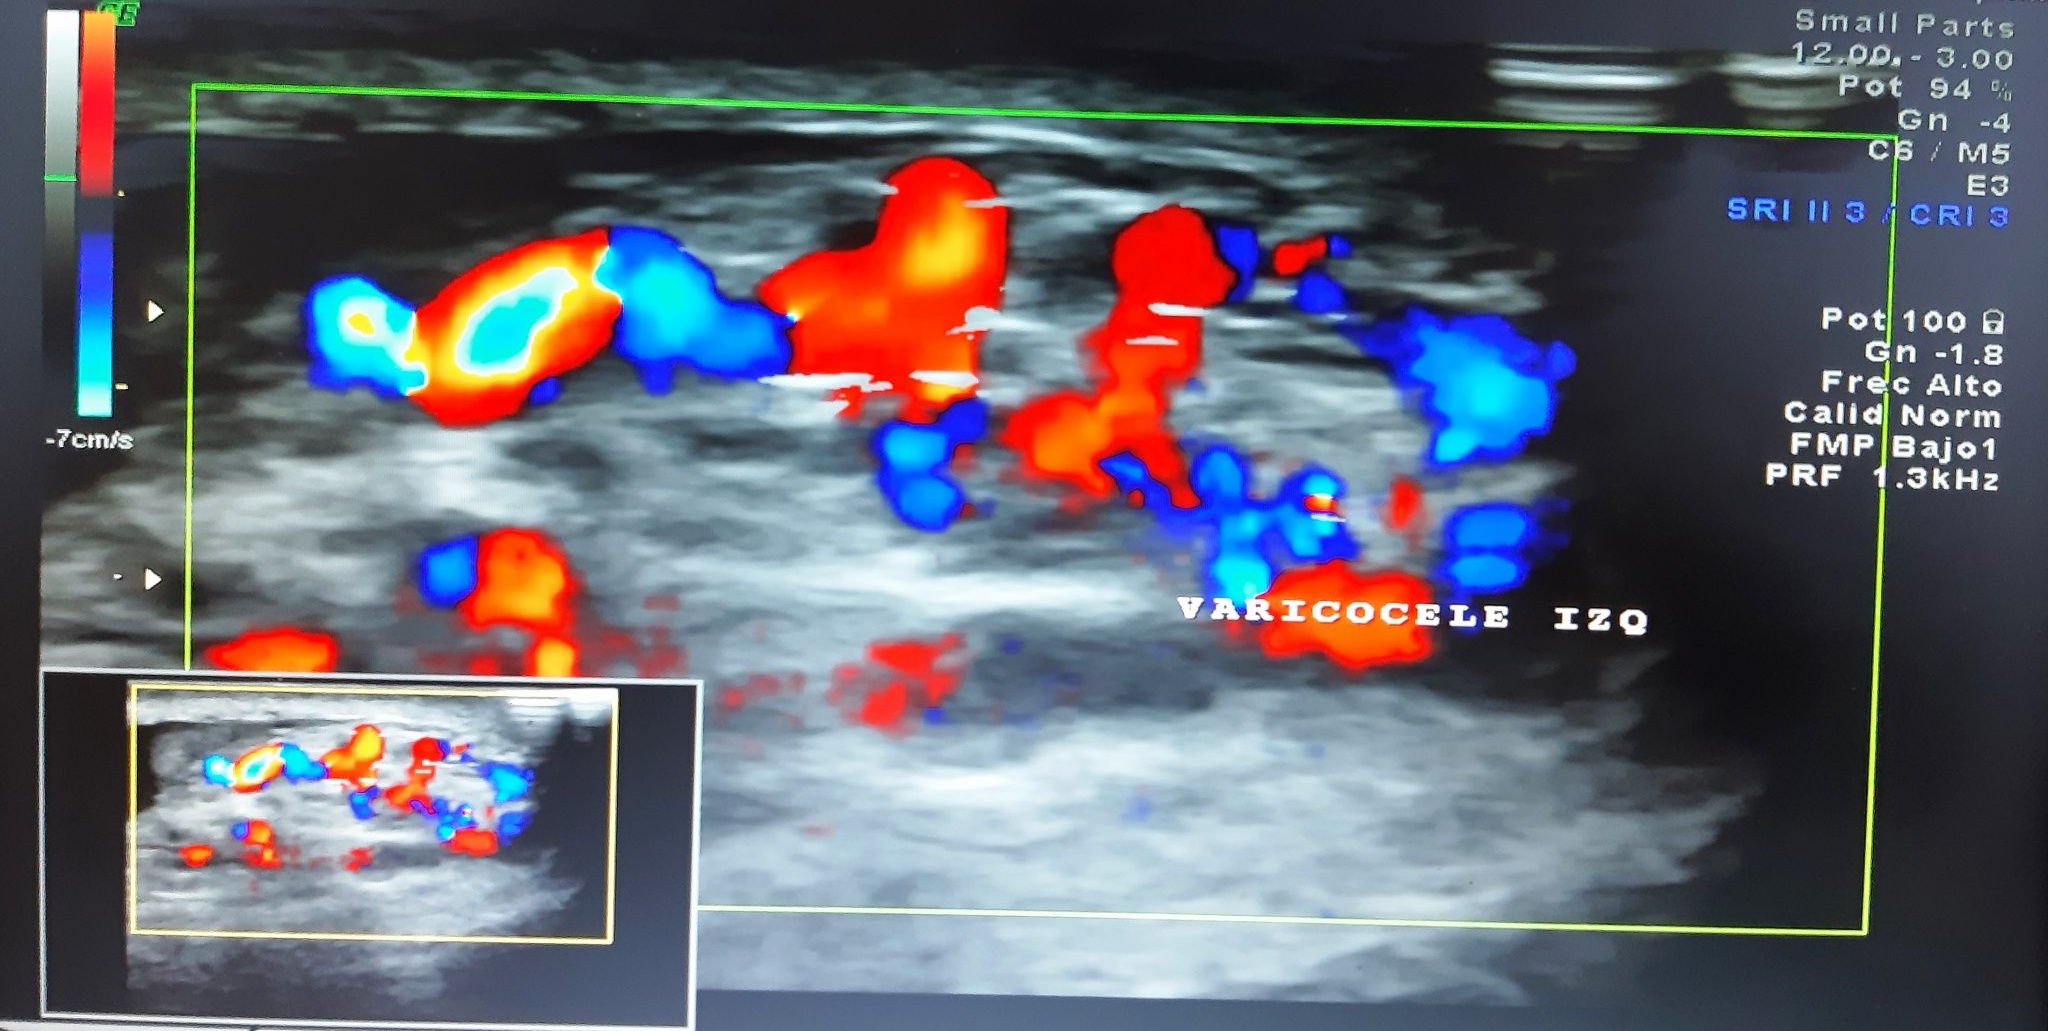

Se diagnostica Varicocele (varices dilatadas en el interior del escroto) por

Ultrasonido observando las varices ya mencionadas, y con Doppler Color, usando una

maniobra de esfuerzo para aumentar la presión intra-abdominal, se mide el mayor

calibre.